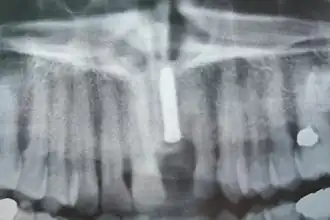

Implants en place. Notez qu'il y a moins d'implants que de dents sur la prothèse.

Radiographie des six implants

Contrôle de la cicatrisation à une semaine de l'intervention